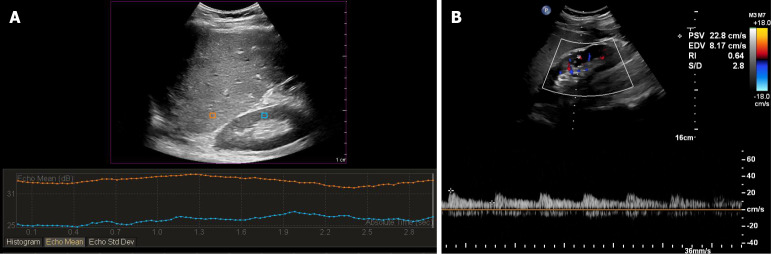

Aim: To investigate the accuracy of hepatorenal index (HRI) and renal resistive index (RRI) in monitoring of early AKI after LT.

Methods: This observational study included adult deceased-donor LT recipients at our center between February 2022 and February 2023 with no preoperative renal dysfunction. The HRI and RRI were recorded once per day in the postoperative period through to postoperative day (POD) 7. We followed up with the patients at 1 month after LT. The patients were divided into the AKI and non-AKI groups according to the Kidney Disease Improving Global Outcomes criteria.

Results: Of 121 patients were included in the study (mean age: 50.18 ± 8.88years; female: 17.36%). AKI developed in 53 patients (43.80%). The AKI and non-AKI groups were similar in terms of their baseline characteristics. An HRI of ≤ 1.12 on POD 1 detected AKI with a sensitivity of 62.30% and a specificity of 87.80% [area under the receiver operating characteristic curve (AUC) = 0.801, P < 0.01]. An RRI of ≥ 0.65 on POD 1 detected AKI with a sensitivity of 87.80% and a specificity of 67.60% (AUC = 0.825, P < 0.01). The HRI combined with the RRI was more effective at detecting AKI than either the HRI or RRI alone (AUC = 0.890, P < 0.01). The HRI increased as AKI resolved while the RRI decreased as AKI resolved.

Conclusion: The HRI and RRI are non-invasive bedside indices that can identify the occurrence and recovery of early AKI after LT.